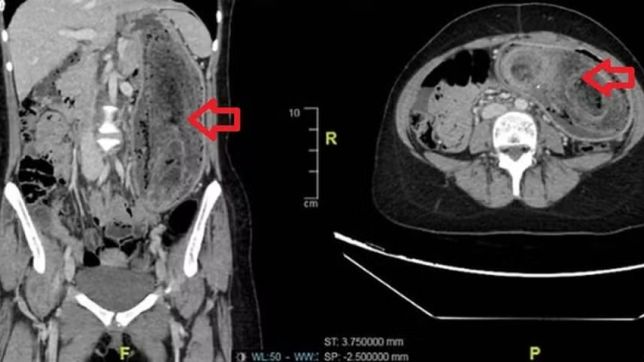

Os médicos notaram que o abdômen estava inchado e dolorido, com uma massa firme palpável. Exames de imagem confirmaram o diagnóstico: um enorme aglomerado de cabelos ocupava todo o estômago e se estendia até o duodeno, o que caracteriza a chamada "síndrome de Rapunzel".

"Devido ao tamanho, não foi possível remover o material por endoscopia. Foi necessário realizar uma cirurgia aberta sob anestesia geral", descrevem os autores do estudo. Durante o procedimento, os cirurgiões extraíram cuidadosamente a bola de cabelo intacta, em uma operação que durou cerca de três horas.